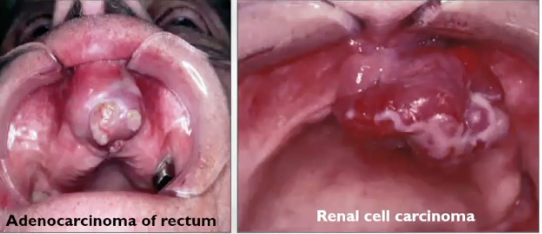

What is metastatic disease?

It is more common of a carcinoma than a sarcoma

What is the difference between carcinoma and sarcoma?

Sarcoma = origin is mesenchymal stem cells (bone, cartilage, adipose tissue, fat, skeletal muscle, smooth muscle)

Carcinoma = origin of the epithelium (most common is squamous cell carcinoma)

If metastatic disease does occur, where will it be?

2/3 are in bone (80% mandible > maxilla)

1/3 in soft tissue (most commonly gingiva)

Common origin of gnathic metastasis:

Breast

Lung

Thyroid

Prostate

Kidney

What is this

Metastatic nasopharyngeal carcinoma

Metastatic small cell carcinoma of the lung